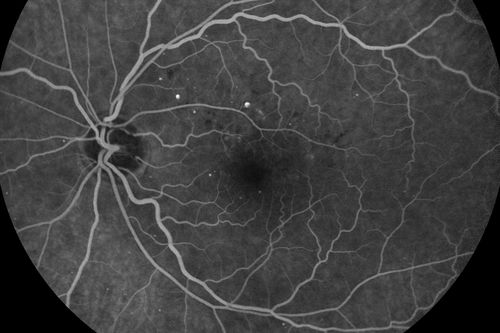

Diabetic Macular Edema - Mild

70 year old man with mild edema did well without treatment